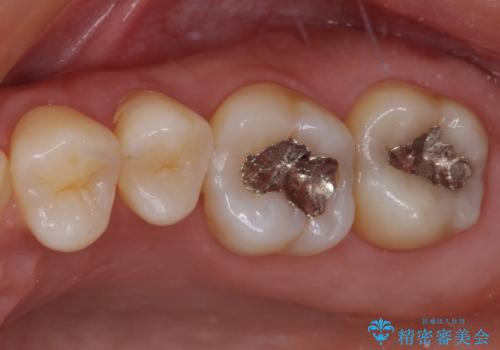

2歯ともに根管治療を行い、その後はオールセラミッククラウンにて補綴治療を行うこととしました。

来院時には食事が取れないほどの痛みを訴えていらっしゃいましたが、処置後からは痛みが軽減され、食事もいつも通りに取れるようになりました。